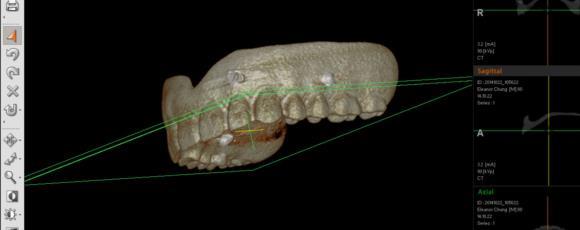

Compare a CBCT taken in 2011 vs in 2015, is there a difference? When is a good time to get a scan? A CBCT Scan is no longer a priviledge but it is a must diagnostic tool in Implant Dentistry. It gives you 3 dimesional view of a site, allows you to estimate proximity of vital structures such as a nerve or a sinus, you can study the anatomy, you can virtually plan a case, with or without a surgical guide.

Saying that scan is not necessary will soon be like stating xray is not essential. New CBCT machines deliver low dosage, fast scans for every clinical need..